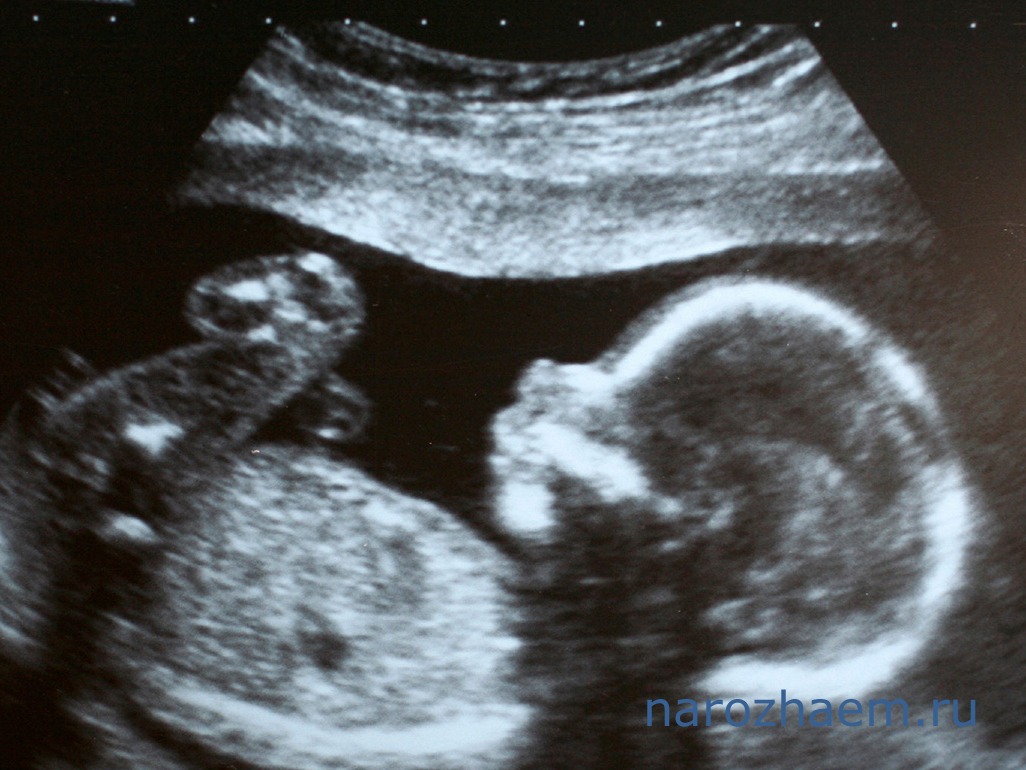

Для беременной женщины первое УЗИ (да и последующие тоже) – это волнующий момент, когда она может посмотреть на своего малыша на самых ранних этапах его развития. Для врача данное исследование – способ оценить как степень и правильность развития будущего ребенка, так и то, как себя «чувствует» плацента и матка (состояние миометрия, шейки матки, околоплодных вод, тонус органа).

Многие женщины, не дожидаясь 10-недельного срока, уже в сроке 5 недель спешат на УЗИ, чтобы на 100% быть уверенными в своем «интересном положении». Чуть позже, в сроке 7-8 недель, можно хорошо увидеть прикрепленное к внутренней стенке матки плодное яйцо, определить активность плода, его жизнеспособность. Врач так же оценивает состояние околоплодных вод и тонус матки.

Чаще всего, первое УЗИ при беременности проводится в сроке 10-12 недель, когда врач может с точностью до 2-3 дней определить день, когда должны наступить роды. В это время оценивается состояние плаценты и место ее прикрепления. Так же смотрится матка и ее тонус, цервикальный канал. Все это необходимо для того, чтобы ведение беременности было максимально правильным. Для исключения генетических патологий измеряется толщина тканей, окружающих шею эмбриона.

На следующее УЗИ женщина приходит в сроке 22-23 недели, когда можно увидеть (или исключить) пороки развития будущего ребенка. Обязательно оценивается развитие плода – соответствие сроков размеру. Обязательно исследуется плацента, околоплодные воды, смотрится тонус матки.

Последнее УЗИ проводится в 30-32-недельном сроке, когда можно посмотреть, какова активность плода. Если необходимо, дополнительно делают допплерографическое исследование сосудов будущего ребенка и плаценты. Если обнаруживаются какие-либо нарушения, или тонус матки повышен, женщине, для сохранения беременности, предлагается лечь под наблюдение в стационар.